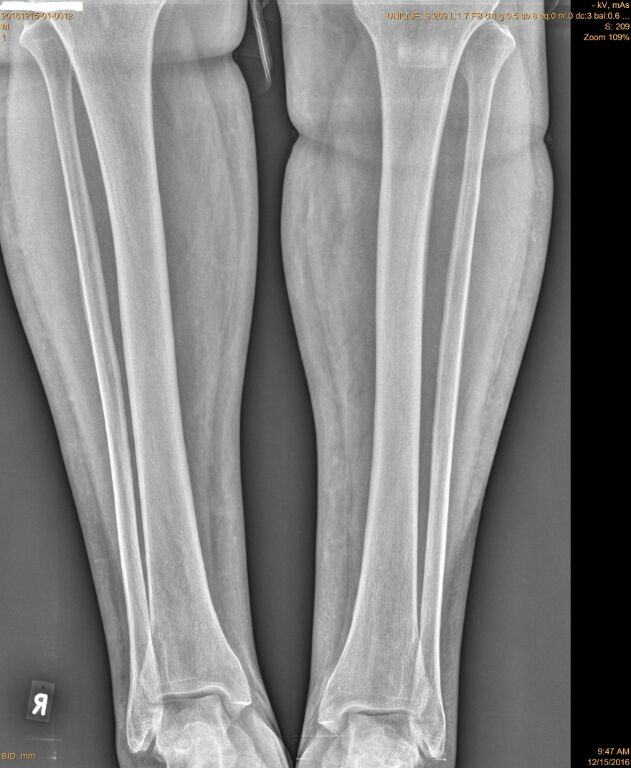

[Ortho] Непонятный свищ

Рентген

Ниязов Нияз